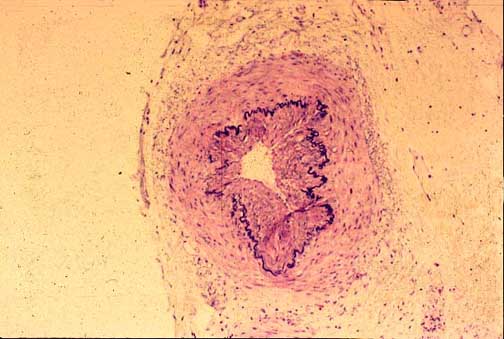

10-1-1.jpg (41289 bytes)

Fig. 10-1-1 Vascular amyloidosis;

Notice in this picture the greenish material accumulated

In the wall of a portal arteriole. The deposition may be

concentric or patchy. Sulfated alcian blue stain.

2-Amyloidosis.

Vascular amyloidosis causes thickening of the arterial wall in intra-parenchymal

hepatic arteries similar to arteriosclerosis. This type of amyloidosis does not

infiltrate the lobular plates of hepatocytes. It is poorly visible with a conventional H&E stain but it should not be missed. An amyloid stain is required.